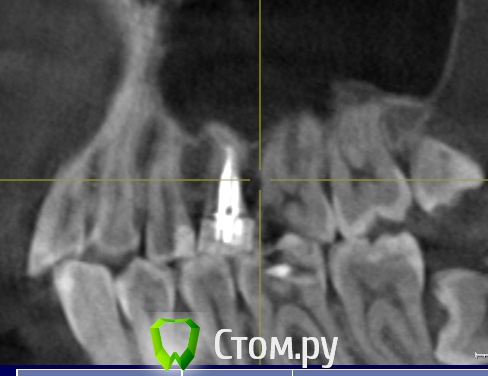

Томатоша Опубликовано 19 февраля, 2014 Поделиться Опубликовано 19 февраля, 2014 Здравствуйте, уважаемые врачи.Прошу прокомментировать, необходимо ли перелечивание каналов в зубе (изображение прикреплено ниже).Корень зуба оказался незапломбированым до конца, из-за его формы, по всей видимости. Зуб не беспокоит, и стоит так уже около 10 лет, а точнее не меньше 10 лет. Велика ли вероятность, что после 10 лет без проблем, в нём неожиданно начнется воспаление? Стоит ли его трогать и перелечивать? При том что, на мой непрофессиональный взгляд, он может просто не выдержать перелечивания. Ссылка на комментарий

Томатоша Опубликовано 19 февраля, 2014 Автор Поделиться Опубликовано 19 февраля, 2014 Здравствуйтеэто скринщот КТ? Надо бы его еще покрутить со всех сторон. Да, на других проекциях вообще ничего не понятно, на мой скромный не профессиональный взгляд. И доктор указала мне на необходимость перелечинания именно на таком срезе, вот на этот незалеченный торчащеий кончик. Я могу выложить весь файл КТ, но не знаю как это сделать, потому что на диске перемешаны файлы установки программы для просмотра и сам файл/файлы КТ. Ссылка на комментарий

АнтонТЛТ Опубликовано 19 февраля, 2014 Поделиться Опубликовано 19 февраля, 2014 Судя по этому срезу, я бы перелечил. Еще есть проблемные зубы, которые нужно лечить. Зубы мудрости удалить. Ссылка на комментарий

АнтонТЛТ Опубликовано 20 февраля, 2014 Поделиться Опубликовано 20 февраля, 2014 на счет нижней 5-ки не могу сказать, качество картинки не очень Ссылка на комментарий